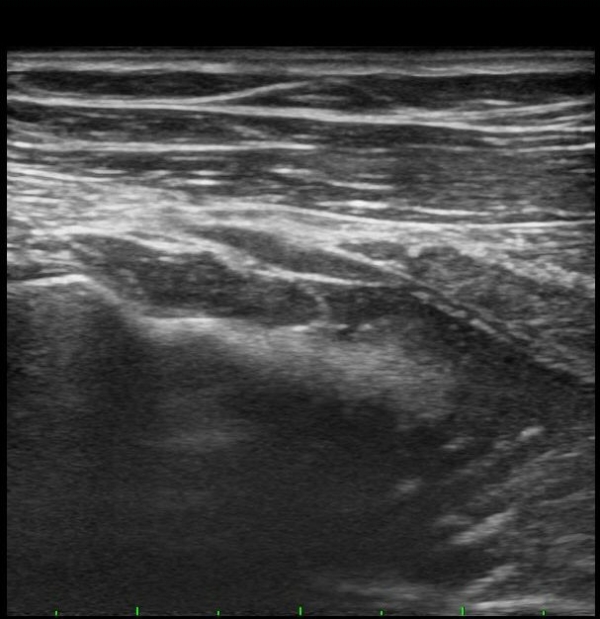

ŽÃËÀÚÀ» ¸»´ÜÀ¸·Î À̵¿ÇÏÀÚ Èİñ°£½Å°æÀÌ È¸¿Ü±Ù ±ÙÀ§ºÎ¿¡¼­ Àú¿¡ÄÚ ºÎÁ¾À» º¸ÀÓ(±×¸² 2).